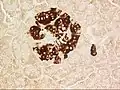

A pancreatic islet, stained.

A pancreatic islet, showing alpha cells

A pancreatic islet, showing beta cells.